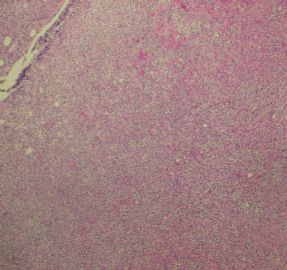

姓    名: ××× 性别:  女 年龄:  77岁

标本名称:  左前臂数个大小不等的皮下肿物。

既往有非何杰金淋巴瘤(滤泡性淋巴瘤)病史22个月。

• 左前臂数个大小不等的皮下肿物     淋巴瘤?图2

图2

病例不错。细胞胞浆透亮,间质血管丰富,图片不是很清晰,似乎有嗜酸粒细胞?

恶性,首先考虑T-NHL。IHC证实。

既往有NHL病史,图片不太清晰,细胞弥漫,胞浆透亮,首先考虑T细胞淋巴瘤。